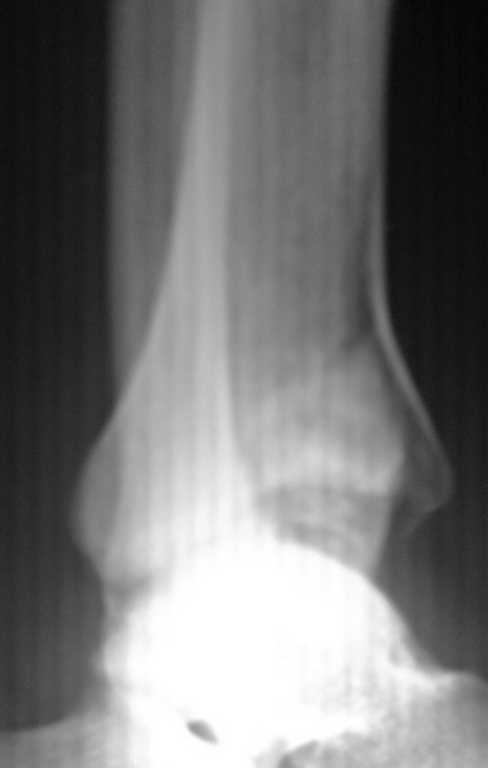

Больной 29 лет , плотник , травма 3 дня назад - упал с высоты 2 метра . Первая помощь в травмпункте одного уважаемого учреждения . Диагноз " З. перелом внутренней лодыжки без смещения ". рекомендовано консервативное лечение. Сегодня госпитализировал в своё отделение , мой диагноз - "Перелом пилона", планирую оперативное лечение в объёме: открытая репозиция , костная пластика после восстановления суставной поверхности, Фиксация Т или L пластиной, используя её в качестве опорной . Сверху АВФ в режиме дистракции с шарнирами для ранних движений.

Более качественные снимки представлю позже . (сломался рентгенаппарат )

А можно вторую проекцию и КТ посмотреть?

Перелом внутрисуставной, с импрессией или переднего или заднего (нужна боковая проэкция) края tibia. Думаю, что пластика нужна, фиксация клевером возможна, но зачем аппарат? Не пересолите, коллега. Да, и предупредить пациента о развитии посттравматического остеоартроза надо обязательно - это потом упростит ваши с ним взаимоотношения.......

Приветствую ! Что то вторая проекция не прошла :((

Пересылаю